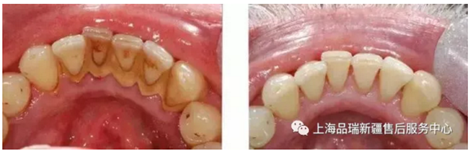

六、洗牙后,牙縫變大、牙齒松動怎么辦?

有這樣的感覺,多半也是因為你牙洗少了。

長期留存的牙結(jié)石會不斷刺激牙齦導(dǎo)致萎縮,當(dāng)牙結(jié)石還在時你感覺不明顯,當(dāng)洗牙后牙結(jié)石被清理掉、牙齦腫脹和炎癥消退,松動就會變明顯。

就像原本裝滿垃圾的房間被清理干凈了,房間并沒變大但是空間變大了。洗牙不但不會造成牙齒松動,反而可以有效預(yù)防和治療牙周炎,防止牙齒松動、脫落。